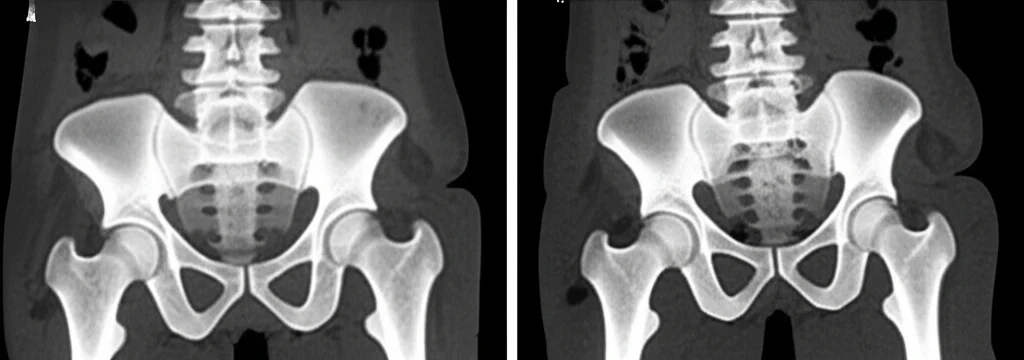

Finora, la prassi comune era quella di esaminare le pazienti in posizione supina, cioè sdraiate. Ma i ricercatori si sono chiesti: “E se la forza di gravità, quando siamo in piedi, cambiasse le carte in tavola?”. Dopotutto, è in posizione eretta che il pavimento pelvico lavora di più per contrastare la discesa degli organi.

Per rispondere a questa domanda, hanno coinvolto 64 pazienti con un prolasso della parete vaginale anteriore o dell utero almeno di stadio 2, che non si erano mai sottoposte a chirurgia per prolasso. Queste donne sono state sottoposte a una RMN sia da sdraiate che in piedi. Per il muscolo pubococcigeo (PCM), si è usato un protocollo di valutazione del danno già esistente. Ma per l ileococcigeo (ICM), udite udite, i ricercatori hanno dovuto sviluppare e validare un nuovo protocollo di valutazione appositamente per questo studio, perché non ne esisteva uno standardizzato!

E qui arriva il bello! Quando si è trattato di valutare il danno al muscolo ileococcigeo (ICM), le differenze tra la posizione supina e quella eretta sono state sbalorditive.

- In posizione supina, solo il 6.3% delle pazienti mostrava un danno maggiore all’ICM.

- In posizione eretta, questa percentuale saliva drasticamente al 51.6%!

Avete letto bene! C’è una differenza statisticamente super significativa (p < 0.001). In pratica, nel 59% dei casi, la valutazione da sdraiate portava a una grave sottostima del danno all’ICM. Immaginate quante diagnosi potrebbero essere state incomplete finora!

Un esempio lampante riguarda le ernie dell’ICM, che sono dei veri e propri “cedimenti” focali del muscolo. In posizione supina ne sono state identificate solo 2 in due pazienti, mentre in posizione eretta ben 27 in 20 pazienti! Questo ci fa capire come la forza di gravità e la postura eretta mettano sotto stress il pavimento pelvico in un modo che la posizione sdraiata semplicemente non riesce a replicare per questo specifico muscolo.